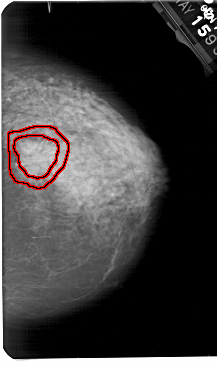

A_1823_1.RIGHT_CC

RIGHT_MLO LINES 5491 PIXELS_PER_LINE 3436 BITS_PER_PIXEL 12 RESOLUTION 43.5 OVERLAY

FILE: A_1823_1.RIGHT_CC.OVERLAY

TOTAL_ABNORMALITIES 1

ABNORMALITY 1

LESION_TYPE MASS SHAPE IRREGULAR MARGINS ILL_DEFINED

ASSESSMENT 4

SUBTLETY 4

PATHOLOGY MALIGNANT

TOTAL_OUTLINES 2

BOUNDARY

CORE